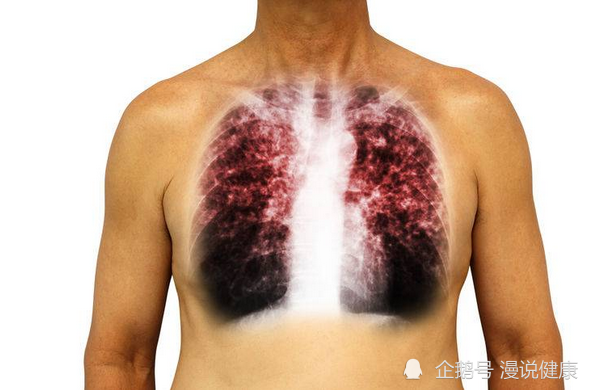

肺这一器官十分娇弱,如果受到外界长期不良因素的刺激,可诱发各种肺部疾病,严重时还可造成肺癌。

肺癌在我国不仅病率高,而且死亡率也是最高的。因此,提起肺癌,大家总会觉得十分恐惧。而为了避免个人的健康以及生命受到威胁,我们有必要了解肺癌的致病因素,从而进行针对性的预防。